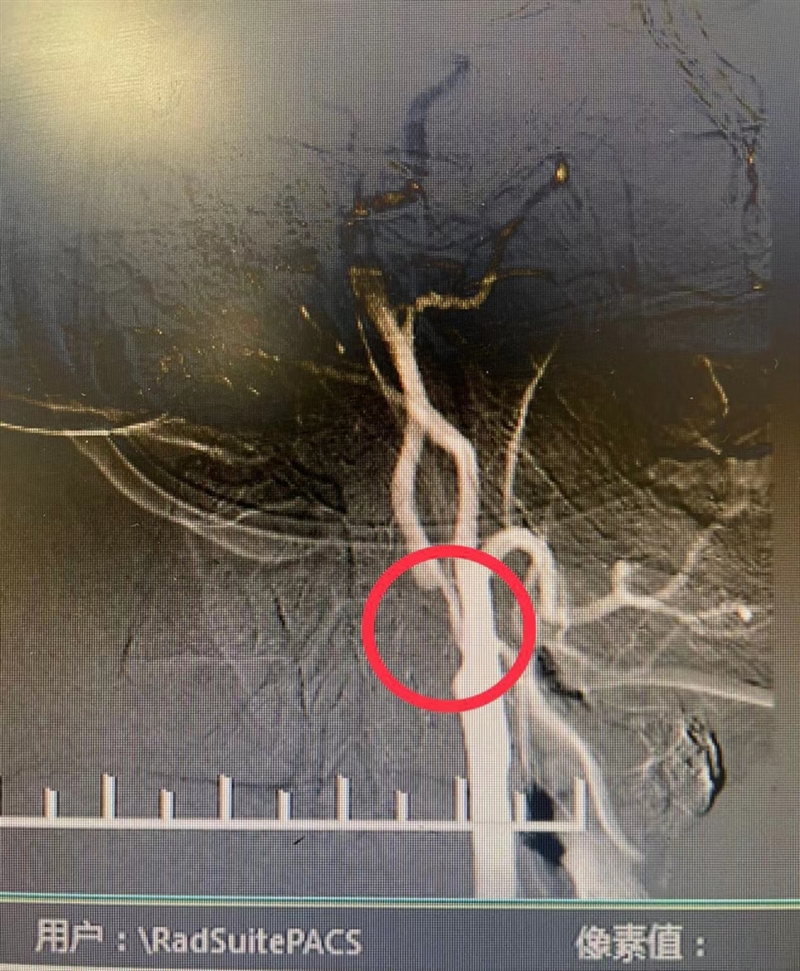

11月8日上午9:15,在麻醉医师实施全麻后,刘国栋主任医师带领陶一浩、赵贯建等医师,正式实施显微镜下右侧颈动脉成形术+颈动脉内膜剥脱术。“先在左侧胸锁乳突肌前缘直切口,暴露颈阔肌、颈总动脉鞘,在触及到颈总动脉末端有质地较硬的斑块后,阻断分叉处近端颈总动脉及远端颈内、颈外动脉;再于显微镜下切开颈动脉壁,完整剥除4cm左右的硬膜斑块并修剪后,连续缝合颈动脉壁;最后,依次短暂解除颈内、颈外及颈总动脉,冲刷管腔后迅速完整缝合颈动脉壁……”因手术团队经验丰富,再加上手术全程使用脑氧监护及电生理监测,大大提高了安全性,两小时后手术顺利结束。术后,经过医护人员的精心治疗,杨红已于近日康复出院。

术前

术后